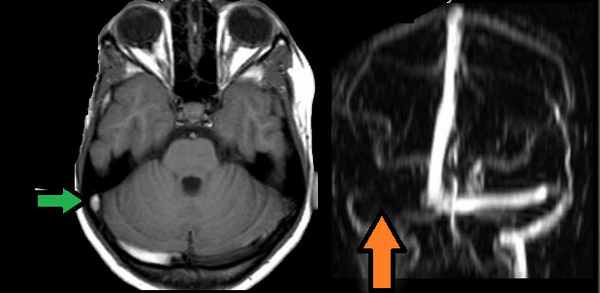

МР-венография: тромбоз правого поперечного синуса. Отмечается потеря МР-сигнала от правого поперечного синуса.

Наличие визуализации синуса на «сырых» данных или же МРТ головного мозга подтверждает тромбоз синуса и исключает его гипо- и аплазию.

Тромбоз правого поперечного синуса. Отсутствие феномена «пустоты потока» от правого поперечного синуса на МРТ головного мозга. Отсутствие визуализации правого поперечного синуса на МР-венографии.

МРТ головного мозга: отмечается сочетание вазогенного (оранжевая стрелка), цитотоксического отека и кровоизлияния (зеленая стрелка). Данная МР-картина, а также расположение патологической зоны в проекции височной доли, заставляет задуматься о геморрагическом венозном НМК вследствие тромбоза вены Лаббе. Для подтверждения необходимо проведение МР-венографии или МРТ с контрастным усилением.